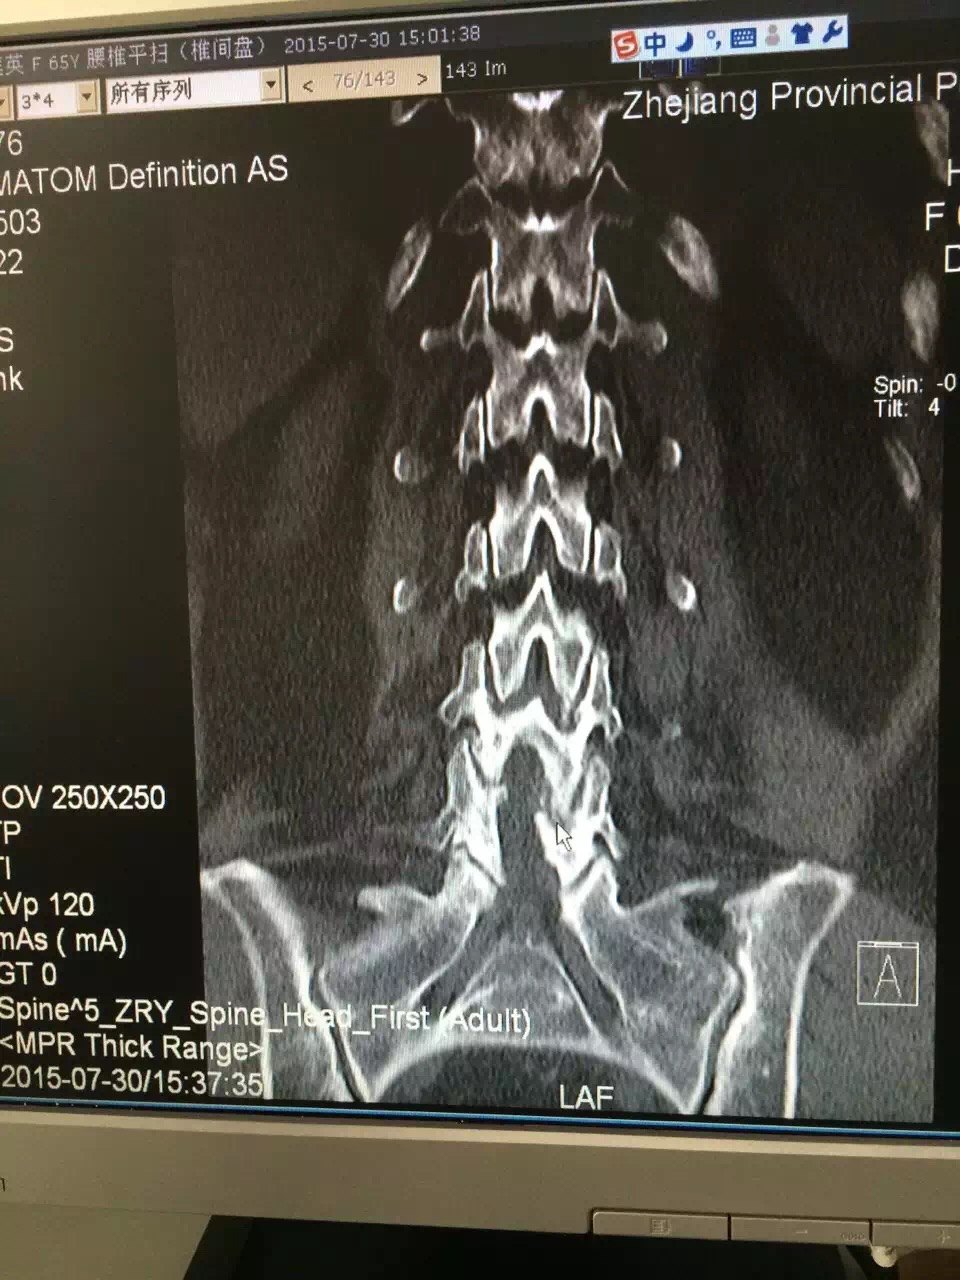

病例:手术治愈多节段颈椎间盘突出症一例

狭窄并腰椎间盘突出症患者实施3d打印多孔金属腰椎椎间融合器植入手术